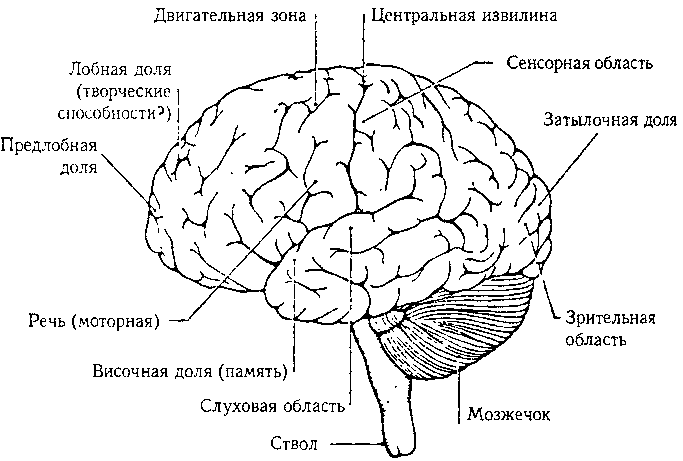

Глава XI: Мозг и мысль. Тема этой главы — «Как физическая аппаратура мозга может порождать мысли?» Сначала описываются крупномасштабные и мелкомасштабные структуры мозга. Затем выдвигается несколько гипотез об отношении понятий к нейронной деятельности.

66. Человеческий мозг вид сбоку.